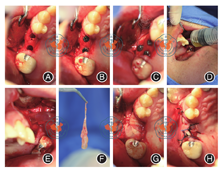

术前抽血25 ml制备PRF以备用。在25、26牙槽嵴顶偏腭侧用定位钻确定种植体植入方向及位置,Bicon系列钻逐级备洞至4.5 mm × 6 mm,收集自体骨屑,常规植入植体2枚(4.5 mm × 6 mm,Bicon,美国),平骨敲击就位。术中25颊侧区见1处约6 mm × 6 mm大小的类圆形骨质缺损,上颌窦囊肿侧壁暴露,囊壁完整,与周围骨质无明显粘连。于25颊侧骨缺损处穿刺抽出约2 ml黄色清亮液体,沿囊壁与骨壁间分离囊肿,完整摘除囊壁,0.9%氯化钠溶液加庆大霉素冲洗上颌窦,25颊侧区骨缺损处放置2片PRF膜,其上覆盖胶原膜1片(2.0 cm × 2.5 cm,海奥口腔修复膜,烟台)。25、26种植体颊侧放入自体骨,表面覆盖PRF膜,严密缝合创口(图5)。术后CBCT示:25、26位置良好,上颌窦内可见21.3 mm × 8.4 mm水平形密度影(图6)。25、26种植术6月后行种植体Ⅱ期手术。CBCT示:25、26骨结合良好,左侧上颌窦清晰,窦壁黏膜无炎性增生(图7)。处理:取出愈合帽,戴入愈合基台。25、26Ⅱ期手术1个月后行全瓷冠修复治疗(图8,图9)。25、26修复完成1年后对植体情况进行复查(图10,图11)。

注:图5A为种植术区备洞;图5B为植入种植体;图5C为术中所见暴露的囊肿,箭头所示25、26颊侧上颌窦暴露的囊肿侧壁;图5D为抽吸出淡黄色囊液;图5E为术中摘除囊肿;图5F为所摘除的囊肿;图5G为自体骨粉充填囊腔后PRF膜覆盖;图5H为缝合创口